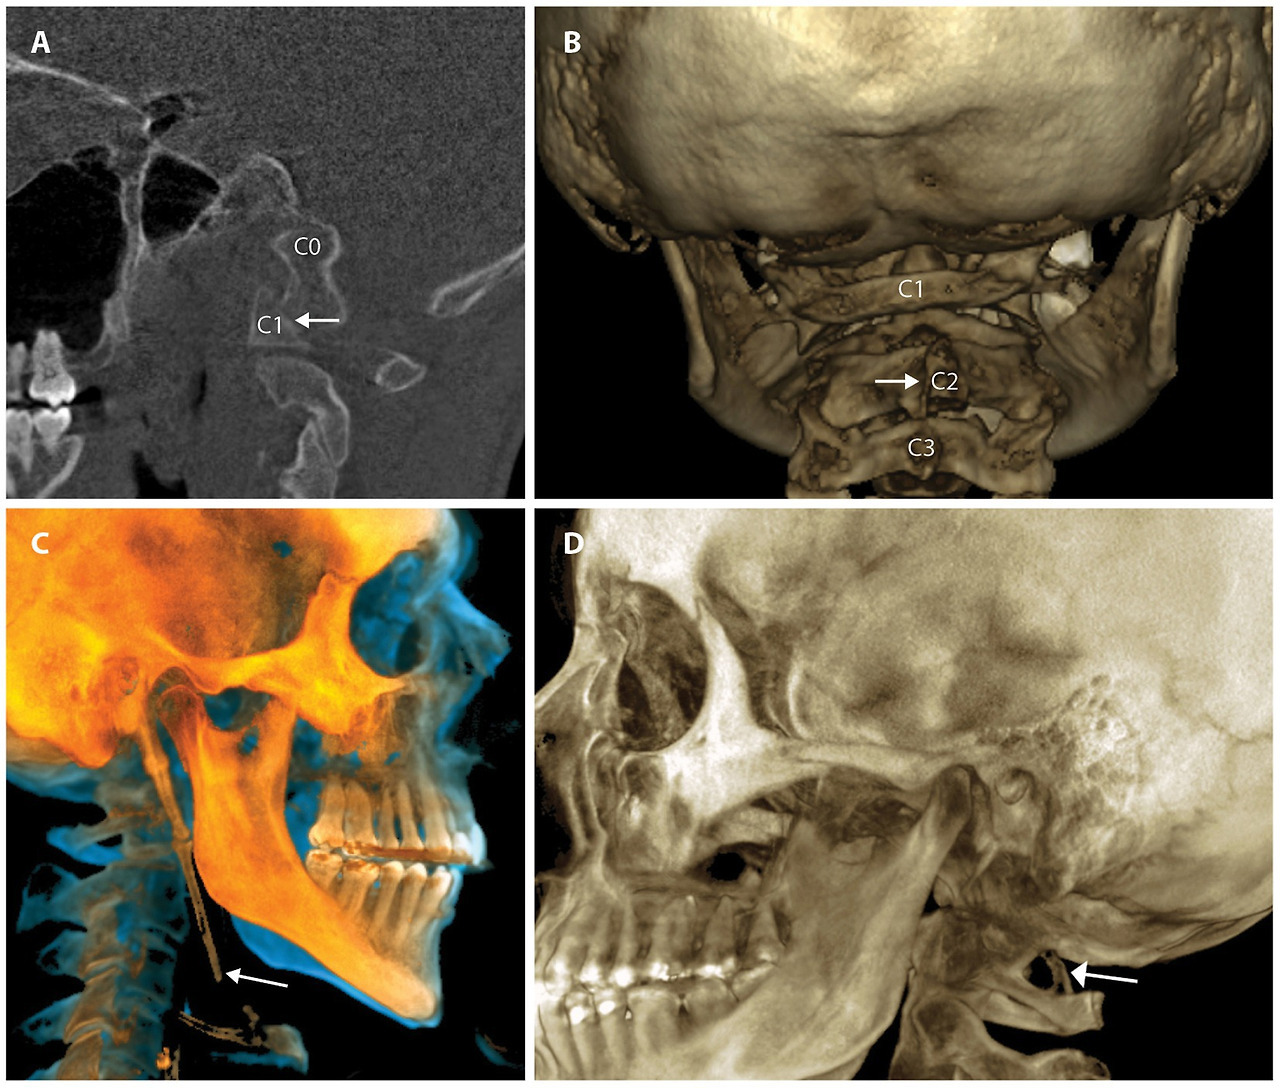

Cervical structural analysis in the upright position and/or with motion allows the clinician to see the motion of vertebral bones in real time and discover previously hidden pathology. The 2 modalities that can be utilized for this imaging are digital motion x-ray (DMX) and upright cone beam CT scanning. Digital motion x-ray (videofluoroscopic) examination of the cervical spine has been shown to provide a high degree of diagnostic accuracy for the identification of vertebral instability in patients with chronic pain stemming from whiplash trauma (54). CT scanning of the cervical spine with 3-D reconstruction in various positions, including flexion, extension, and/or rotation, is another way to document cervical instability and misalignments that are missed by more traditional means (55). Cone beam CT scanning can document elongated styloid bones, which can compress the carotid sheath, and thus the IJVs, with head rotation and flexion (see Figure 6).

Figure 6

Figure 6. Common pathology seen by upright cone beam CT scan of head and neck. (A) CO-C1 instability. (B) Cervical spine misalignments. (C) Elongated styloid. (D) Ponticulus posticus.